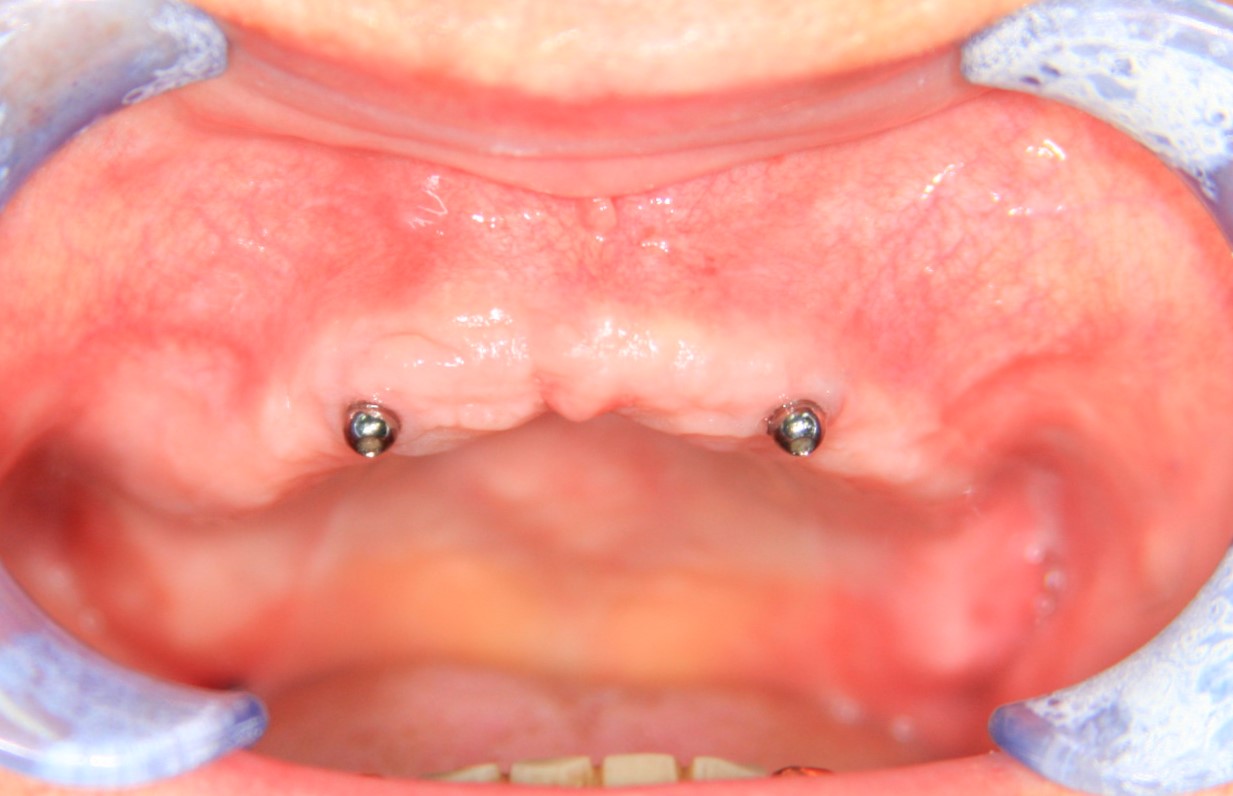

Напомню, что 85-летнюю бабушку беспокоит то, что у неё съёмный протез выпадает. С учётом её возраста и состояния здоровья, её необходимо простое и наименее травматичное решение. Поэтому мы поставим бабушке два имплантата со специальными замками, к которым будет фиксироваться съёмный протез.

И всё! Протез не выпадает, бабушка счастлива!

Тут есть еще один бонус. Поскольку протез теперь держится за счёт имплантатов, а не «вакуума», мы можем убрать пластик с нёба и значительно уменьшить его размер. Сам протез перестал болтаться, стал более удобным. Бабушка счастлива вдвойне!